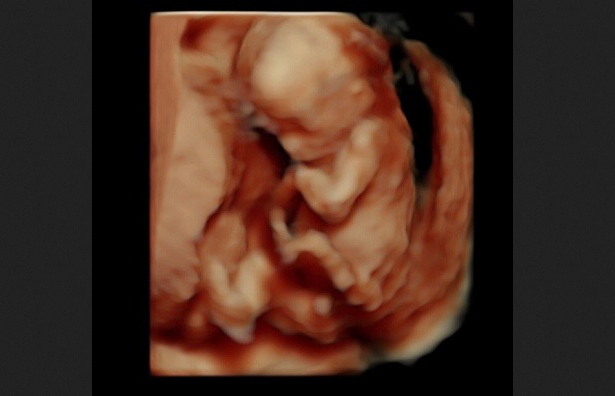

“This is flat out drug dealing. … There is no doctor-patient relationship whatsoever. These are people who are writing these prescriptions and sending them to anybody who asks, don’t know where they’re going, and there is no relationship — period,” Murrill continued. The previous rules governing the prescription of mifepristone required abortion drug manufacturers “to have a contract with a doctor that prescribed these medications, and they had to comply with these elevated FDA rules which required in-person dispensing and ultrasound and post care,” she explained. “All of those things meant you needed an individual personal relationship with a doctor. You don’t have that anymore. And it is illegal to use those pills here for an abortion. So every one of those are illegal abortions being practiced in our state without any medical supervision whatsoever.”

In 2023, then-President Joe Biden and his administration eliminated many of the few remaining safeguards, requiring no in-person physician visits, no physician to prescribe the drug, no dispensing or consuming the drug in-office, no follow-up visit, and no reporting of complications. Murrill called the Biden-era changes “entirely arbitrary.” She explained, “The data has always been there, [warning] that this is dangerous for women. That’s why the protocols are in place in the first place. Women can get sepsis if they have a partial abortion, [and] that happens in a significant number of these cases.” The Louisiana AG explained that abortion drugs can and do cause serious complications, including hemorrhaging and even death, in some cases. “There [are] all kinds of contraindications also for women to not take these pills. That’s why you were required to see a doctor, have an ultrasound, and also have some follow-up care if, in fact, you were using these.”